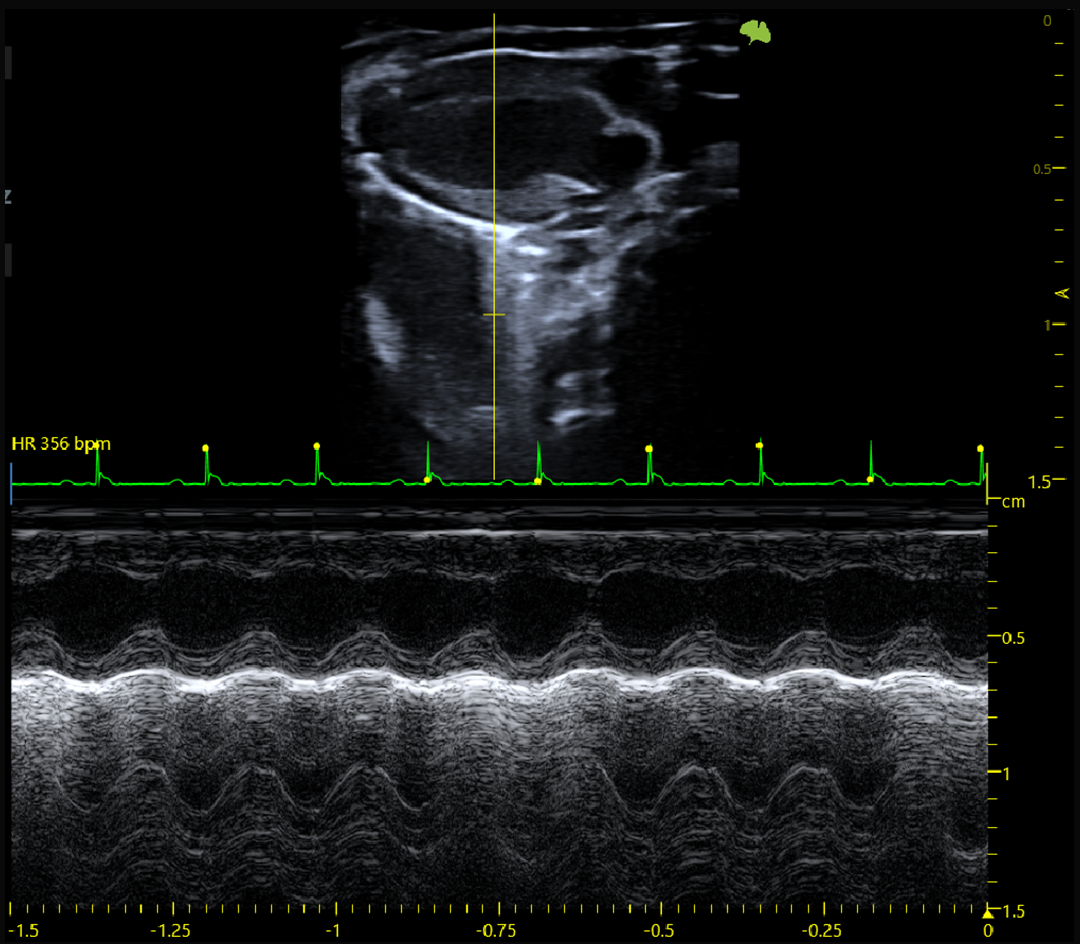

Fonction systolique et diastolique

Imagerie cardiaque haute cadence chez la souris et le rat

ECG intégré

M-mode précis pour l’analyse fonctionnelle cardiaque

Résultat : une imagerie fine, stable et quantitative, adaptée à l’étude de la fonction cardiovasculaire, du flux sanguin et des structures tissulaires complexes.